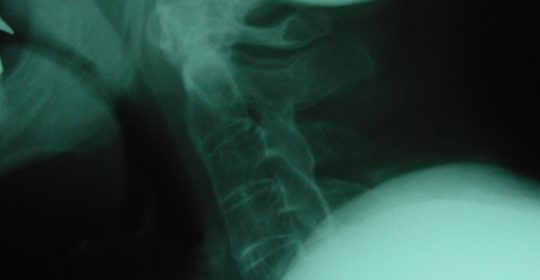

Εικόνα 1 : Απλή πλαγία μετατραυματική ακτινογραφία της Αυχενικής Μοίρας της Σπονδυλικής Στήλης (Α.Μ.Σ.Σ.). Παρατηρείται ότι λόγω της αγκυλοποιητικής σπονδυλίτιδας υπάρχει οστεοποίηση του προσθίου επιμήκους συνδέσμου και δεν είναι δυνατόν να φανεί όλη η Αυχενική Μοίρα της Σπονδυλικής Στήλης (Α.Μ.Σ.Σ.) λόγω της ανύψωσης των ώμων.